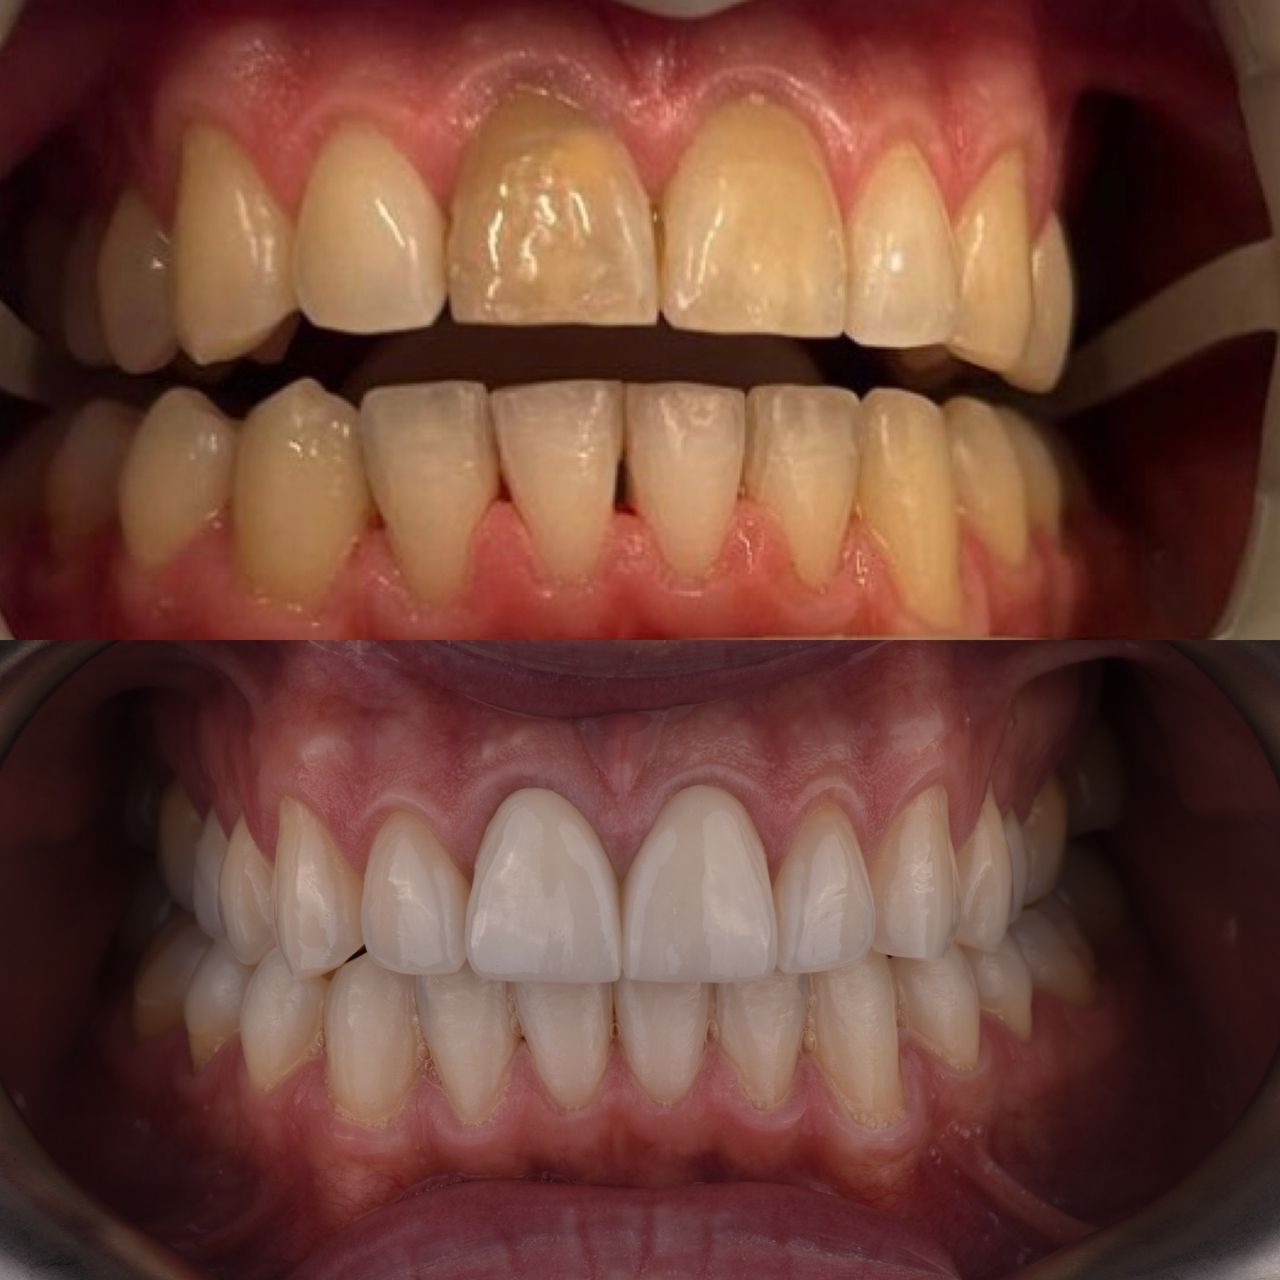

- protetyka (korony ceramiczne (cerkon, E-max), licówki, mosty, protezy ruchome, korony na teleskopach, inlay, onlay, overlay, endkorony);